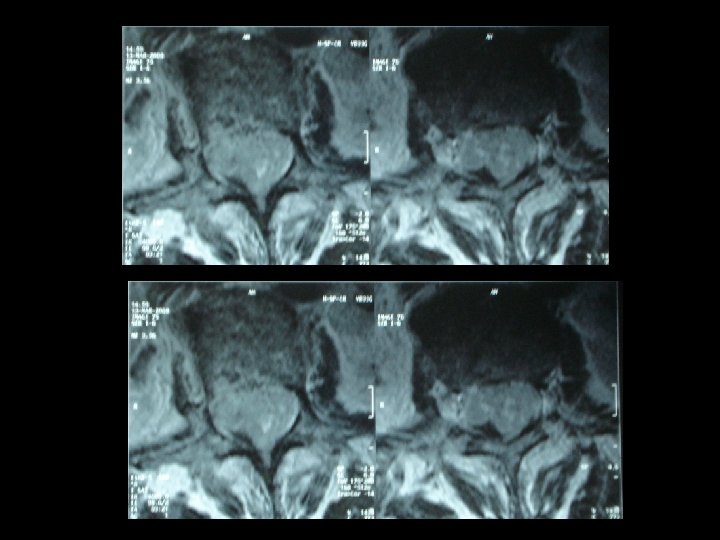

* Les examens biologiques misent en évidence une thrombopénie , une hypo albuminémie et une hypergammaglobulinémie modérée. Sérologie VIH était négative. * L’IRM lombaire pratiquée en séquence T 1, T 2 et avec injection du gadolinium montre un important épaississement des racines de la queue de cheval visible sur les coupes en séquence. T 2 qui se rehaussent intensément après injection du gadolinium.

* La présentation clinique n’est pas spécifique. * IRM médullaire : processus expansif étagé comprimant la moelle par endroit. * les lésions sont e hypo signal T 1, hyper signal T 2 et se rehaussant après injection du gadolinium. * l’IRM joue un rôle primordial dans le diagnostic des lymphomes à localisation médullaire.